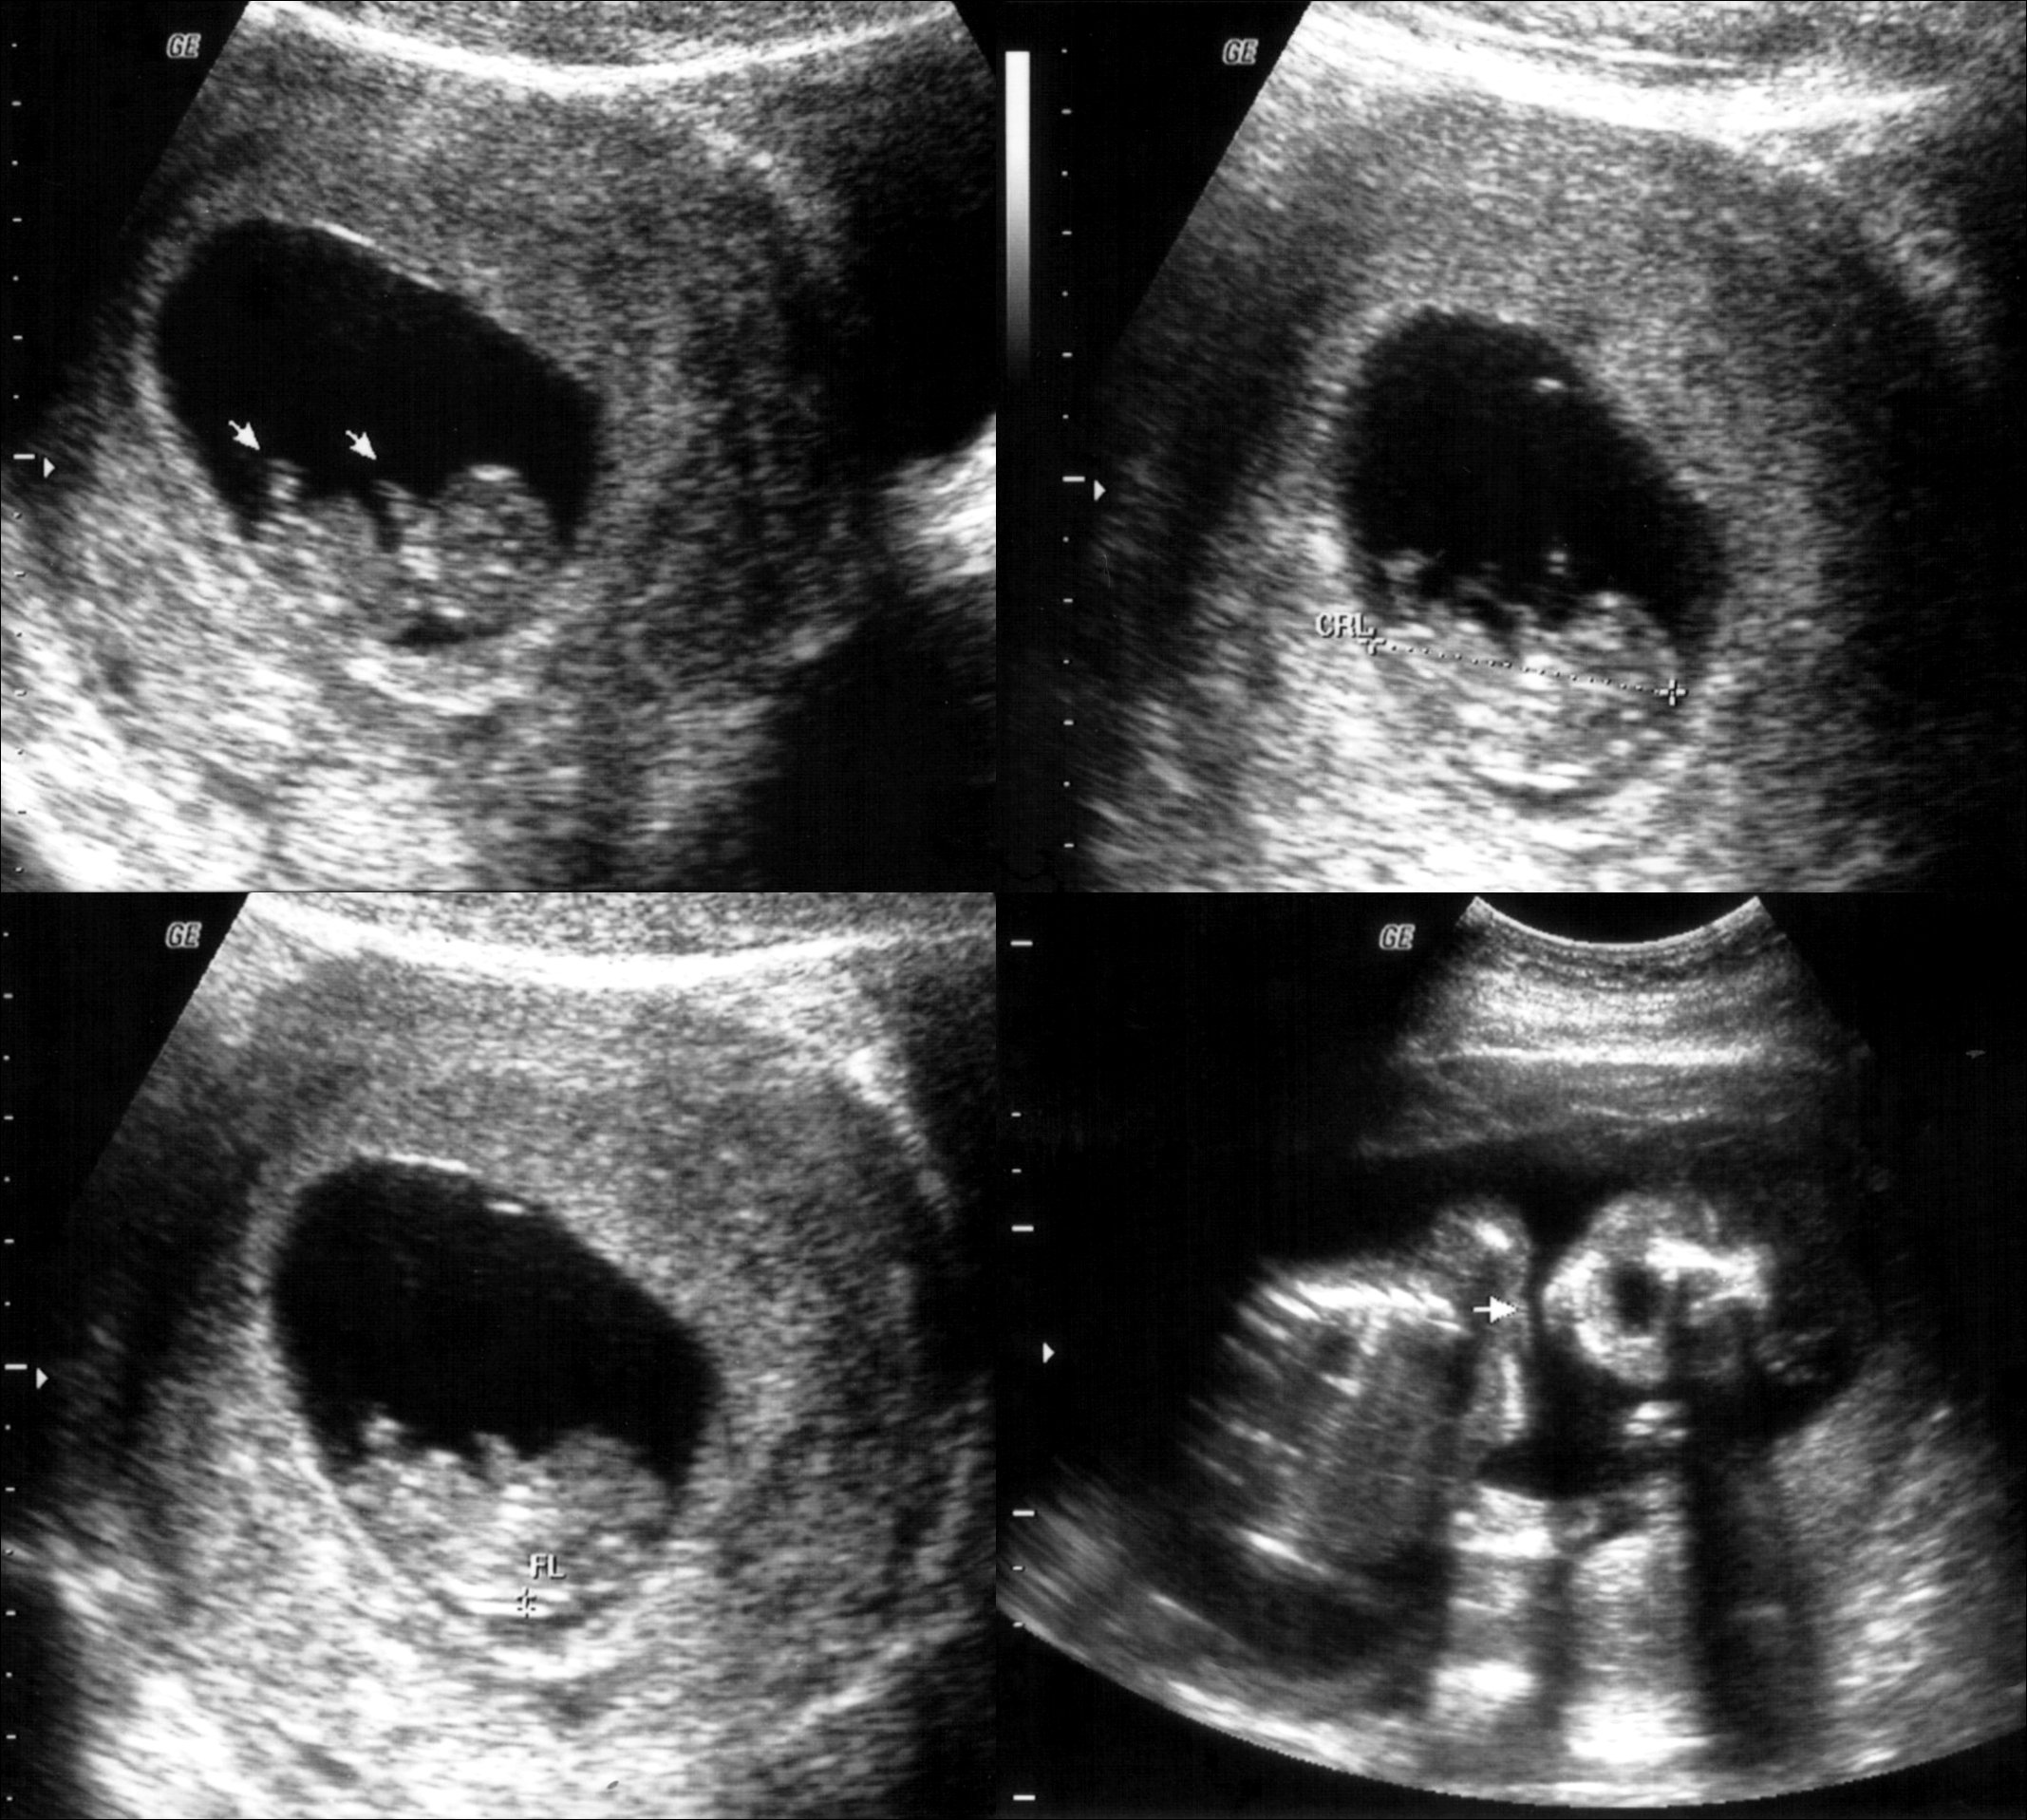

Apparently, on the first appointment the “patient” would pay between ¢ 20,000 and ¢ 30,000 to be evaluated and to have an ultrasound. Soon after she was explained about the process of abortion.

In the house officers found a machine for ultrasound, a stretcher for gynecological examinations, computer equipment, electronic storage devices, surgical tools, important documentation for research and ¢ 300,000 in cash.